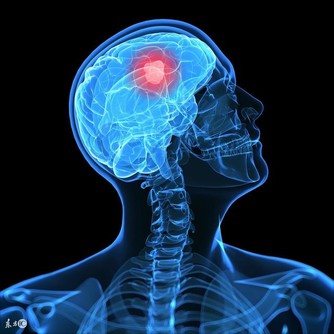

8、免疫系統

生氣時,會阻礙免疫細胞的正常運轉,使免疫功能下降、抵抗力減弱,易感冒,白細胞下降,常發病並過早衰老。